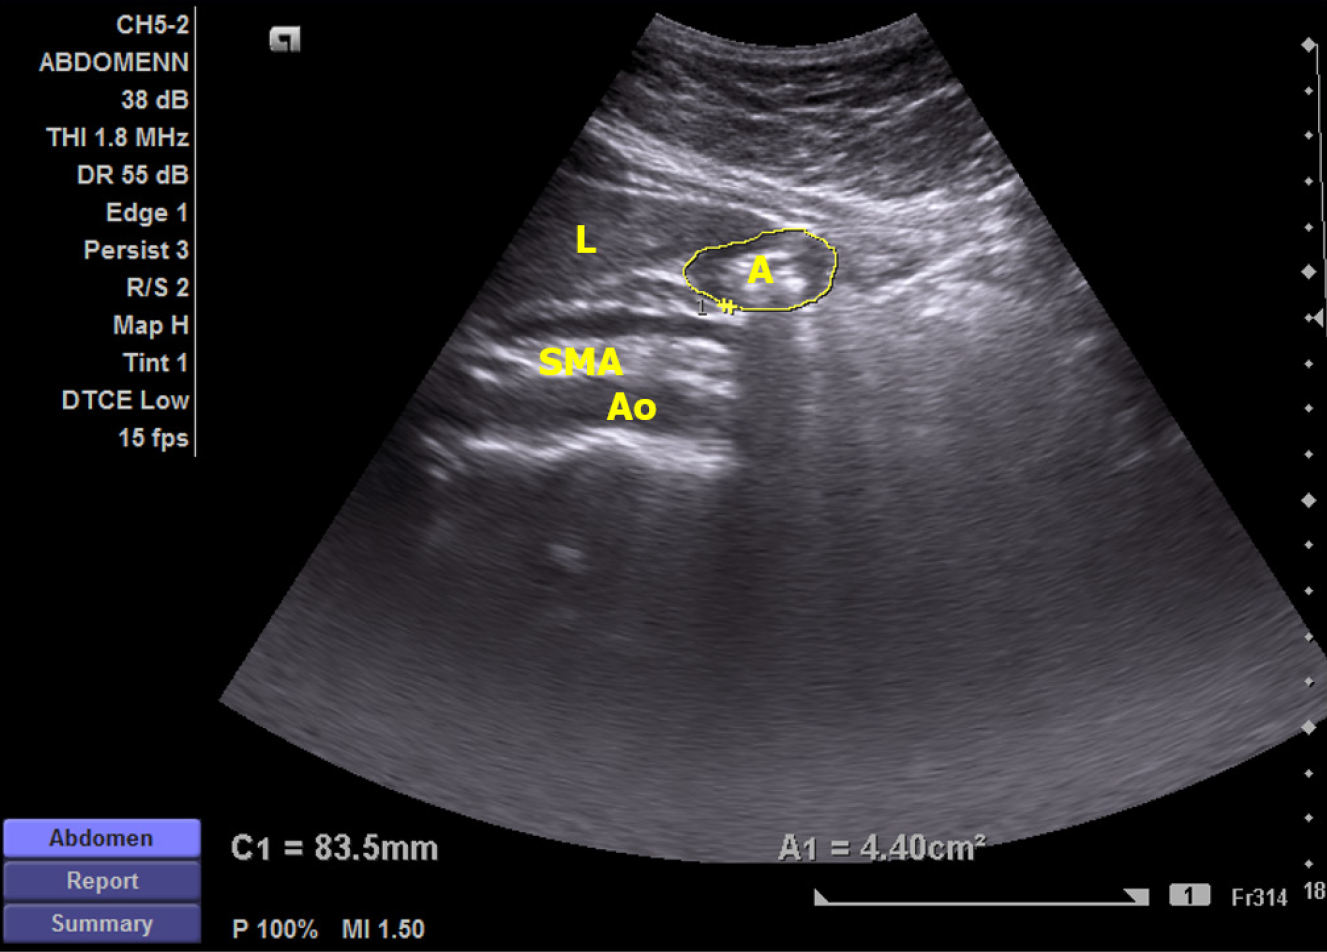

Figure 1 Ultrasound view demonstrating the anatomical plane for antral cross-sectional area measurement.

A: Antrum; Ao: Aorta; L: Left lobe of the liver; SMA: Superior mesenteric artery.